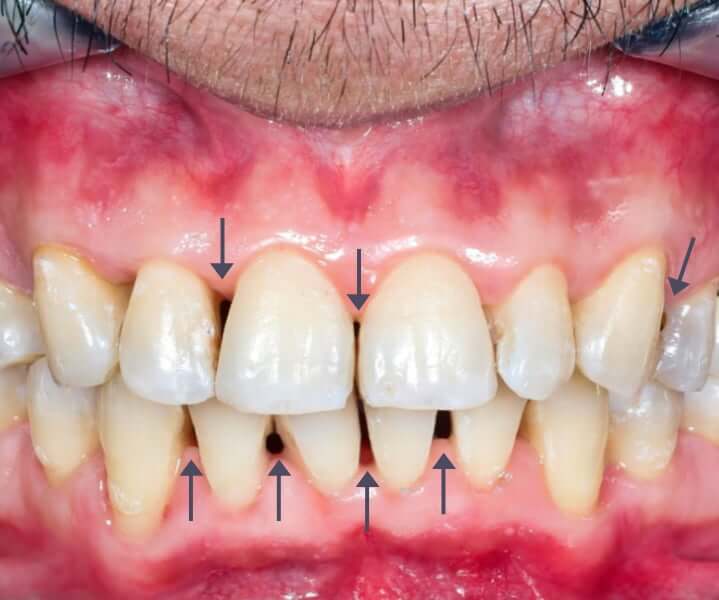

Caso de troneras dentales antes y después relacionado con bruxismo

En ocasiones, las troneras dentales no aparecen de forma aislada, sino que están relacionadas con otros problemas funcionales de la boca.

Este fue el caso: el paciente acudió a consulta porque llevaba tiempo sufriendo molestias constantes en la boca y dolor mandibular sin saber cuál era el origen.

Tras realizar un diagnóstico completo, detectamos que padecía bruxismo y trastornos en la articulación temporomandibular (ATM).

La presión continua provocada por apretar y rechinar los dientes había generado desgaste en algunas piezas dentales y alteraciones en el contacto entre ellas.

Como consecuencia, comenzaron a aparecer troneras dentales visibles entre los dientes anteriores, además de dolor, tensión y sobrecarga muscular.

Una vez identificado el origen del problema, se inició el tratamiento para corregir este hábito nocivo y rehabilitar la estructura dental.